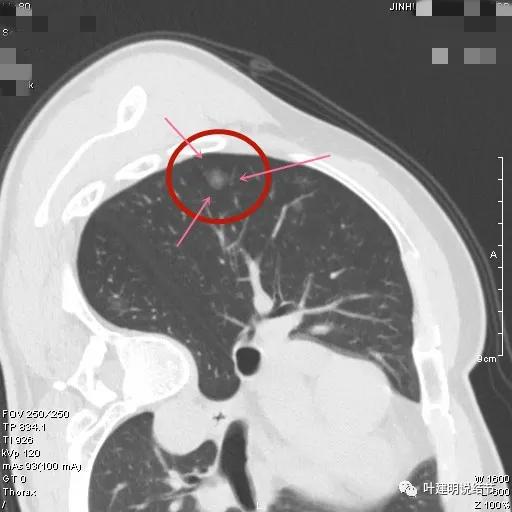

金华的某A,女性,今年43岁,检查发现左肺上叶结节2月余。其于当时说是在外院检查发现,到我门诊找我看过的(我是记不清楚了),大概是告诉她:考虑早期肺癌可能性大,但密度还低,边缘显模糊。让她再随访观察下再决定手术与否。这次送孩子上大学后,她马上来医院全面检查并若需要手术就决定手术了的。我们先来看她的平扫片子:

可见左肺上叶磨玻璃结节,边缘略显模糊,瘤肺边界不是很清,但总体上看,病灶轮廓仍是较为清楚的,而且有所层面有微小血管进入,病灶密度也不均匀,感觉有点杂乱。这种病灶如果随访了2个多月仍持续存在,也没多少变化的话,基本上要考虑肿瘤范畴的结节。为了看细节,我们建议其再查了靶扫描,图像如下: